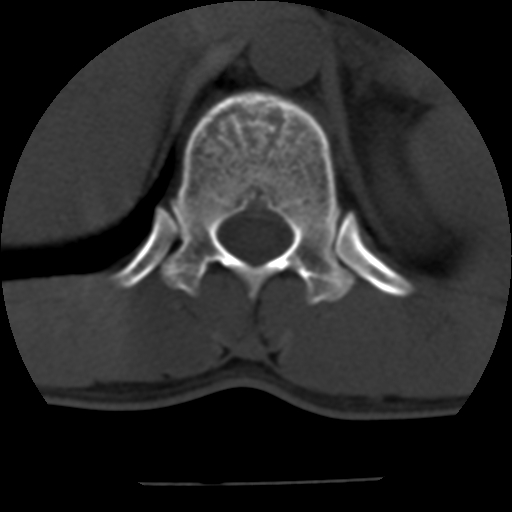

标题: CT10387:男,31岁,胸腰段CT [打印本页]

男,31岁,从6米高处坠落伤两天,腰背部疼痛,临床要求ct扫描胸10-腰1。请大家帮忙看看骨质有问题吗?

t12、l1锥体前缘轻度楔形变,平扫示椎体前缘骨小梁欠规整,第9幅图示椎体前缘骨质不连续,结合外伤史考虑椎体轻度压缩骨折。

楼主扫描层厚可能较大,每个椎体只有三个层面.

从所示层面分析,无明确骨折征象,象类似病人我个人会建议mri除外骨挫伤.

从上查骨窗第九片椎体前缘皮质显示断裂.压缩骨折?